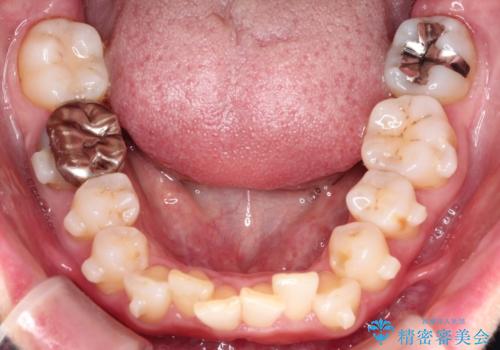

【インビザライン】前歯の凸凹を治したい

- 前歯の凸凹を主訴に来院されました。

臼歯部の遠心移動を行いながらスペースを作り、インビザラインにて前歯をきれいに並べることができました。

今回の治療計画では臼歯部の遠心移動とIPRを行っています。